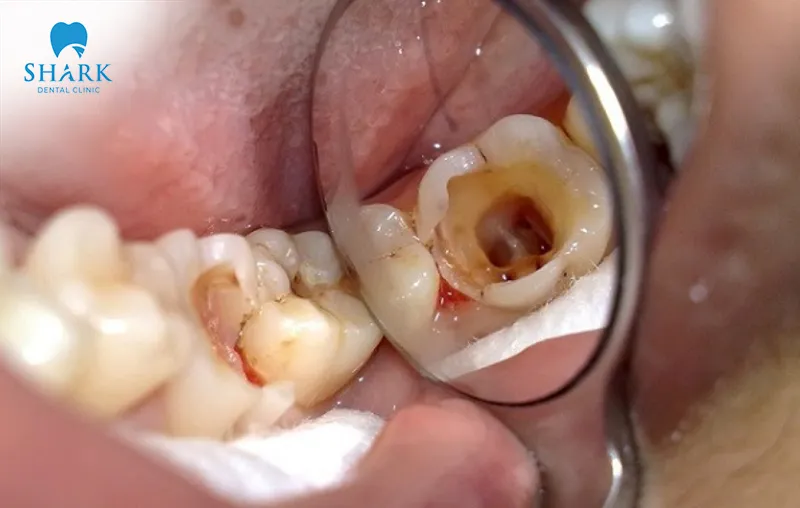

According to dental experts, a crown can indeed get infected. A dental crown infection may occur if the procedure is not performed according to proper protocols, if inappropriate techniques are used, or if the dentist lacks sufficient clinical experience. Additionally, crown infections can arise from improper post-treatment care and inadequate oral hygiene, which can negatively affect overall oral health.

An infected dental crown not only causes pain and discomfort but can also pose serious risks to overall health. More importantly, an infection following crown placement can impact the underlying natural tooth, disrupt daily activities, and significantly impair chewing function.

A common cause of crown infection is an incorrectly sized crown. If the crown does not fit properly, it can create excessive pressure on the tooth root and nerves. Poor crown adaptation leaves gaps between the crown and the natural tooth, allowing bacteria to accumulate. This creates a high-risk environment, leading patients to ask “How common is decay under a crown” in such cases.

During crown placement, the dentist must follow precise and safe techniques. Excessive tooth reduction can damage the natural tooth structure and pulp, while insufficient tooth preparation can expose crown margins. Both situations increase the risk of infection and post-treatment complications.

If underlying oral issues, such as tooth decay or gum inflammation, are not adequately addressed before crown placement, complications may arise afterward. In these cases, crown infection and irritation can occur because the underlying dental diseases were not fully resolved prior to treatment.